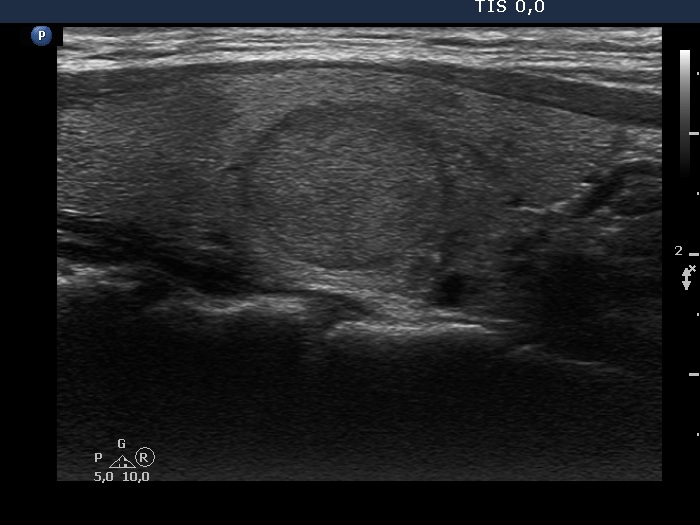

Study on 100 consecutive patients with thyroid nodule - case 030 (ultrasonographic picture 7)

Left lobe, longitudinal scan.